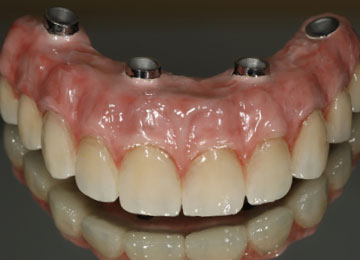

Имплантация зубов: фото "До" и "После"

All-on-4

All-on-6